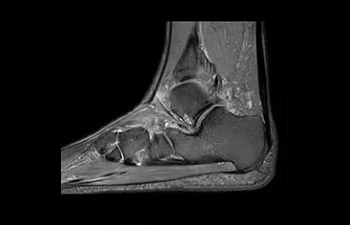

• Baanbrekende versnellingstechniek waarmee niet alleen sequenties versneld worden, maar uw gehele MRI-onderzoek. • Unieke implementatie waarmee 2D- en 3D-scans tot wel 50% sneller gemaakt kunnen worden met een nagenoeg gelijkwaardige beeldkwaliteit.1

• Kan gebruikt worden in alle anatomische contrasten en alle anatomieën.

met Compressed SENSE